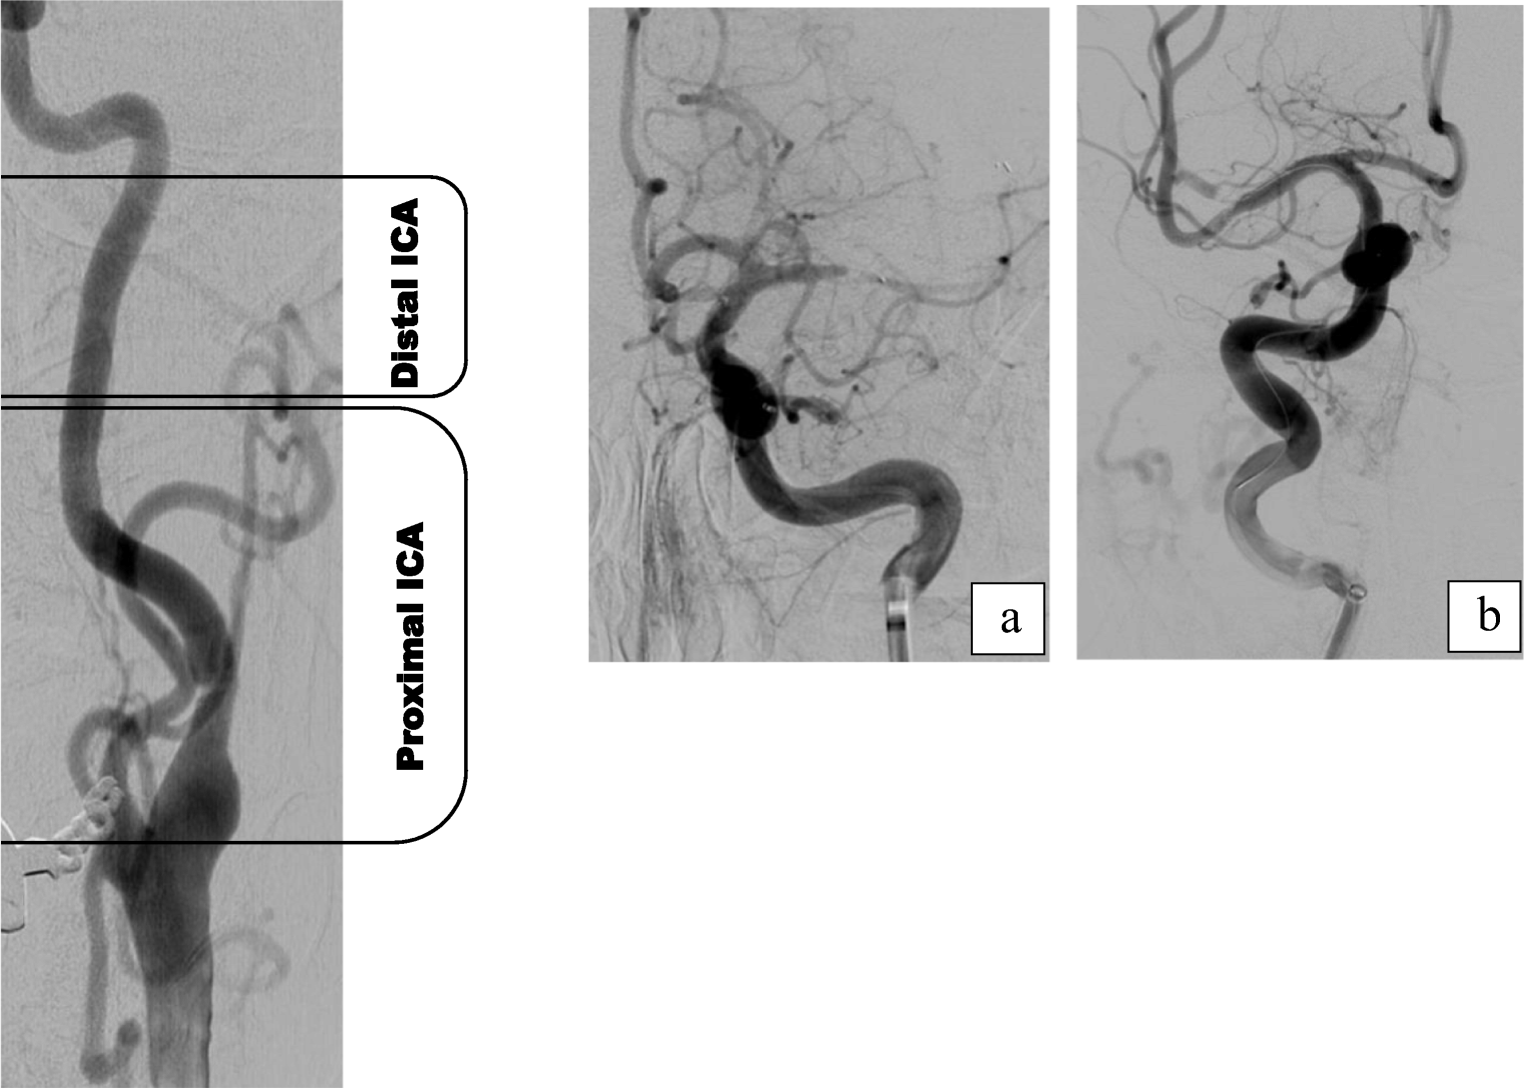

The anatomy of the CoW ipsilateral to the stroke side was determined from the invasive angiographic images on record and correlated with the features of the CTA images to obtain a final evaluation. Variations in diameters between the MCA and the ICA were determined as the ratio of the diameter of the ICA (measured distal to the posterior communicating artery (PCoA) segment) to that of the proximal M1 segment. Elongation of the carotid artery was defined on the basis of such angiographic features as the presence of kinking or tortuosity of the ICA distal to the position of the BGC (Fig. 1), as proposed by Jeong et al. [13]. BGC positioning for treatment was classified into three groups based on dividing the ICA into three segments: (1) the distal ICA (BGC tip located in the distal third of the ICA, i.e., subpetrosal placement), (2) the proximal ICA (BGC tip located in the caudal two thirds of the ICA), and (3) the distal common carotid artery (CCA) (Fig. 2).

Fig. 1

ad Frontal and oblique views of carotid elongation using digital subtraction angiography (DSA). Four examples of internal carotid artery (ICA) elongation distal to the tip of the balloon guide catheter (BGC). In all these cases, the BGC was placed in the proximal ICA (dividing the ICA into three segments from the subpetrosal segment to the extracranial bifurcation, the proximal ICA is the caudal two thirds of the cervical carotid). Case A shows occlusion of the middle cerebral artery and a single 90° kink. Case B shows double ICA kinking and an open retriever device in the distal M1 segment into the M2 segment through a distal M1–M2 clot. Cases C and D depict multiple ICA kinks (the follow-up angiography after recanalization in case C was inadvertently performed under balloon inflation)